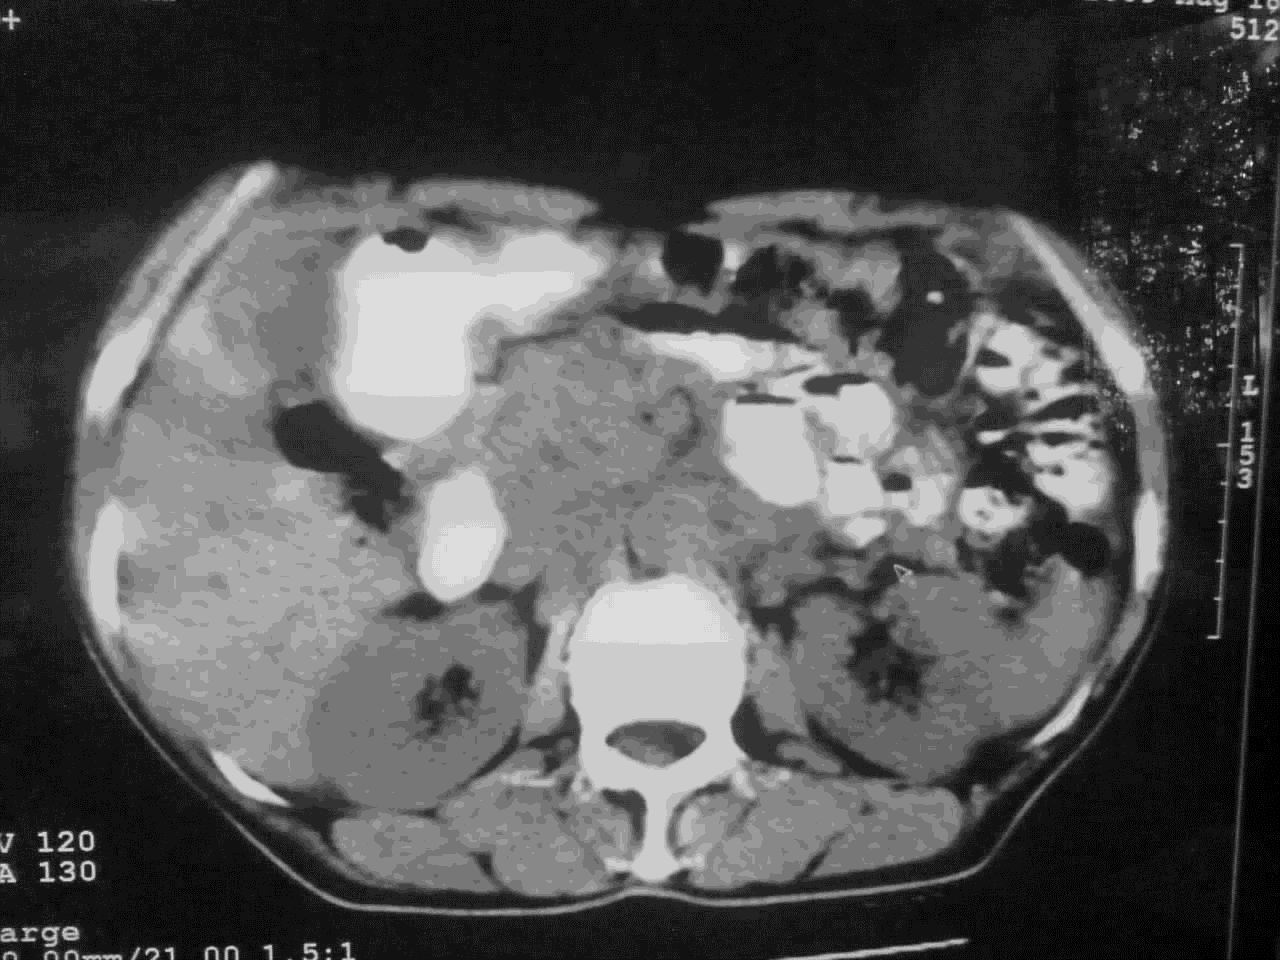

我这个考考大家眼力,看看是升结肠ca还是降结肠ca

好象是横结肠占位肝转移,胰头占位?【伙计,您的片也真够意思】

横结肠占位肝转移

伪影太多,考虑降结肠癌伴肝转移,胆囊炎

伪影太多,考虑升结肠癌伴肝转移,胆囊炎

考虑升结肠癌伴肝转移;胆囊炎。

结肠占位并肝及腹膜后淋巴结转移。

考虑升结肠癌伴肝转移;胆囊炎